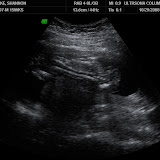

Regardless of my state of mind, LBB looked perfect. Right away I knew I was going to get a boy determination when she told me the heartrate--it has been a steady 160 but this time it was 139. I looked at Josh and said, "I think you're going to win." He was sitting pretty still for awhile, even though I had SO MUCH sugar today. I think I must've put him in a coma! After pushing around a little he started moving and that was amazing to see. We got some cute shots of his little hands and feet and, of course, the package.

| 15 wks |